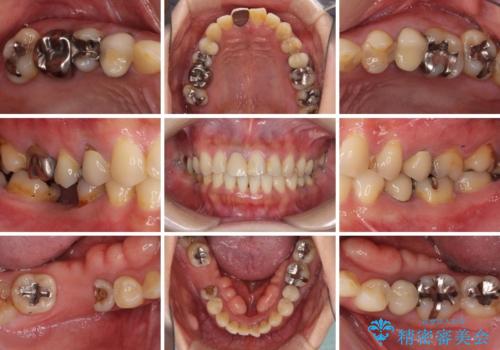

気になる部分を全て治療 総合歯科治療で口腔内環境改善

- 右下の欠損部の治療を希望して来院された患者様です。

部分矯正を行った後にインプラント埋入と手前の歯の根管治療を行い、その後補綴治療を行うこととしました。

治療途中より、上の歯や反対側の銀歯、上顎前歯の色合いや下顎前歯のデコボコが気になってきたため、全てを治療することとしました。

- 治療費の目安: 230万円費用は治療当時の料金となります

仕事が多忙な方で、来院間隔が開いてしまうことが多く、治療期間はかかりましたが、来院回数は最小限で終えることができました。